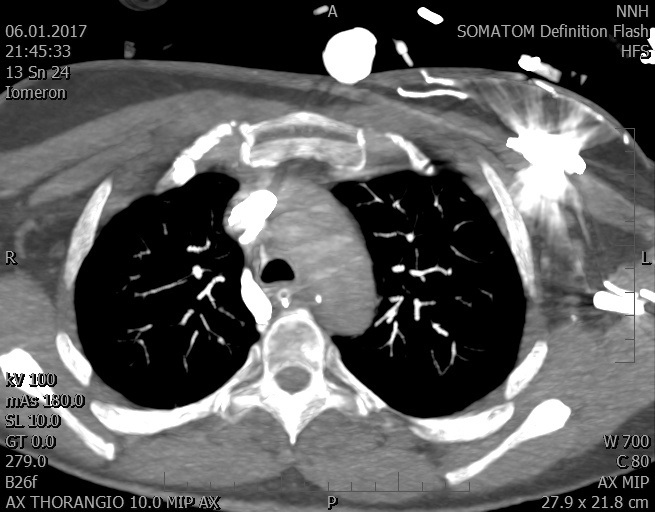

Video 1 - Akutní koronarografie prokázala normální nález na věnčitých tepnách s výjimkou suspekce na lehký spasmus na pravé koronární tepně.Echokardiograficky byla zjištěna těžká dysfunkce dilatované levé komory s nezvětšenou pravou komorou (video 2).

Video 2 - Echokardiograficky byla zjištěna těžká dysfunkce dilatační levé komory s nezvětšenou pravou komorou.Pro nejasnou příčinu zástavy jsme provedli i vyšetření výpočetní tomografií (CT), které vyloučilo plicní embolizaci (série 1 - soubory na konci článku). V den přijetí při přetrvávající oběhové nestabilitě byla nemocná opakovaně defibrilována pro fibrilaci komor se stabilizací rytmu po podání amiodaronu a mesocainu. Dle hemodynamických měření se jednalo o těžký kombinovaný šok. Vstupní laboratorní vyšetření bylo bez větších pozoruhodností. Posléze jsme doplnili anamnézu od příbuzných a zjistili, že pacientka užila do dvou hodin před srdeční zástavou první tabletu amoxicilinu na lehký respirační infekt. Při nevýtěžnosti vstupních vyšetření a nových anamnestických informacích jsme doplnili 14 hodin po kolapsu vyšetření koncentrace tryptázy v séru, která byla extrémně zvýšena (tabulka 2), což nás vedlo k podezření na anafylaxi.